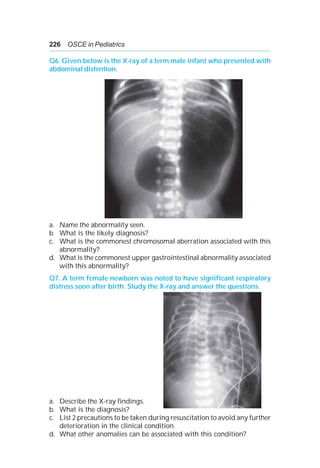

pediatric OPD with complaint of back pain.

a. What is the diagnosis?

b. What extent of above disease causes cardiopulmonary compromise?

c. What is the definitive indication of surgery in this diagnosis?

d. List four conditions which can be associated with this diagnosis.

Q32. Identify the cardiac disease on the basis of the chest X-ray in this

neonate.